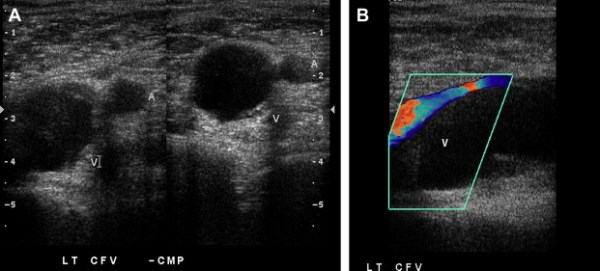

Trong các nghiên cứu tập trung, lớn, độ chính xác của siêu âm ép đối với huyết khối tĩnh mạch sâu có độ đặc hiệu 95% tới 98% và độ nhạy 88-100 % (8).

Các dấu hiệu chẩn đoán siêu âm của huyết khối cấp tính tĩnh mạch sâu bao gồm: không thể ép xẹp các tĩnh mạch và nhìn thấy huyết khối. Huyết khối có thể trống âm, giảm âm hoặc tăng âm.

Hình 2. Huyết khối hoàn toàn tĩnh mạch. Các hình cắt ngang tĩnh mạch khoeo phải cho thấy tĩnh mạch không thể ép xẹp được do có huyết khối cấp tính .